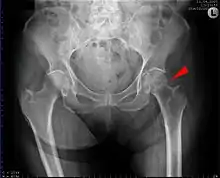

Subcapital fracture in a 92-year-old woman

Fracture (black arrow, pertrochanteric) versus a skin fold (white arrow).

X-rays of the affected hip usually make the diagnosis obvious; AP (anteroposterior) and lateral views should be obtained.